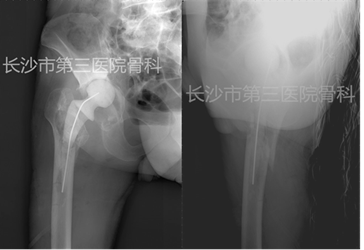

二期翻修术后X片

术后患者疼痛缓解,体温三天后正常。右大腿中上段肿胀较前消退,皮温不高,压痛(-),右下肢纵向叩击痛(-)。术前Harris评分:75。

术中所取标本病检示:右股骨髓腔内组织,镜下见炎性肉芽组织,部分区域可见变性,坏死

术后一周实验室复查(2014-10-26): ESR:67mm/h,CRP:30.6ng/L,PCT:<0.05ng/ml。

术后两周实验室复查(2014-11-3):ESR:61mm/h,CRP:29.6ng/L。